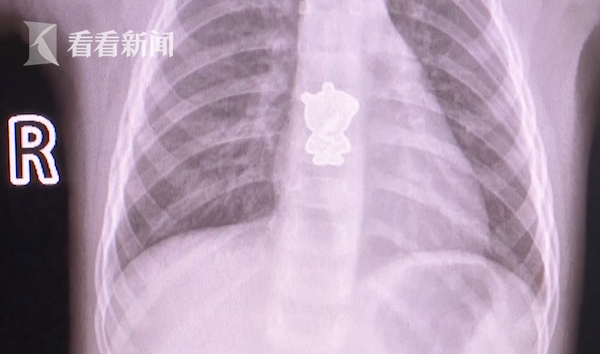

12月24日早上,湖南长沙一岁女童悦悦(化名)起床后一直哭闹不止,家长怎么也找不出原因,于是赶紧将其送往医院检查。医生通过CT检查发现,孩子体内竟藏了个“小猪佩奇”?